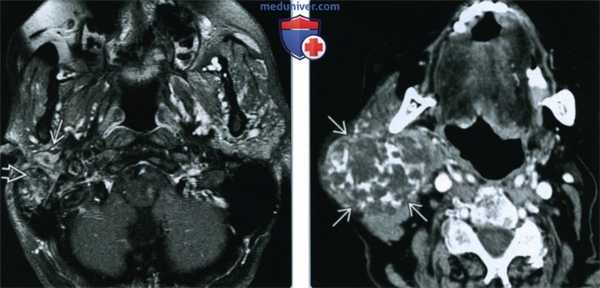

(Слева) На аксиальной МРТ (Т1ВИ С+ FS) в глубокой доле околоушной железы определяется большая опухоль с бугристыми краями, равномерно накапливающая контраст. Шиловидный отросток вдавливает задний край новообразования, что свидетельствует о нахождении опухоли (ДСО) в околоушном пространстве.

(Справа) На аксиальной МРТ (Т1ВИ С+ FS) в глубокой доле околоушной железы определяется опухоль неравномерно накапливающая контраст. Контрастирование ДСО варьирует: может быть равномерным, неравномерным, минимальным.

(Слева) На аксиальной МРТ (Т1ВИ) в глубокой доле левой околоушной железы визуализируется грушевидное объемное образование с промежуточным сигналом. Окологлоточный жир смещен кпереди и кнутри. Отсутствует жировая пластинка между опухолью и глубокой долей околоушной железы, что свидетельствует об истинной интрапаротидной ДСО.

(Справа) На аксиальной МРТ (Т2ВИ FS) определяются множественные мелкие образования в ложе удаленной правой околоушной железы. Рецидивирующая ДСО обычно множественная и напоминает виноградную гроздь.